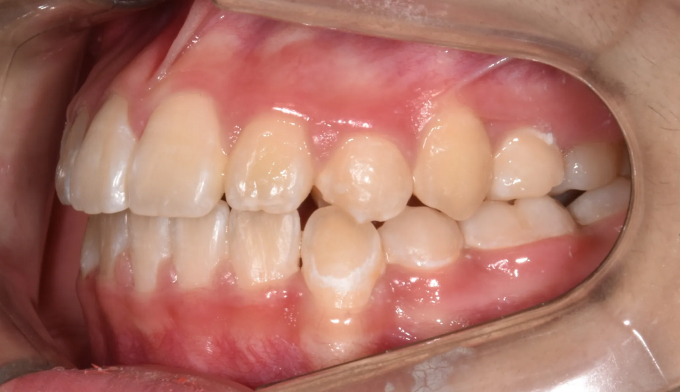

송곳니가 원래 나와야 할 공간이 없다보니 작은 어금니 위치로 이동해서 맹출하고 있습니다. 이를 치아 전위라고 합니다.

이와 더불어 좁은 위턱 악궁은 얼굴 전체의 비대칭을 유발하고 있고, 아래턱의 과성장은 주걱턱 경향까지 보이고 있습니다.

아래턱의 과성장이 심해지고 있어서 절충치료로 아래치열을 배열해줍니다.

이미 송곳니와 작은어금니의 위치가 꽤 많이 바뀐 상태에서 치과에 내원하게 되어 어쩔 수 없이 최종적인 위치를 바꿔서 배열합니다. 씹거나 말하는데는 전혀 문제가 없습니다.